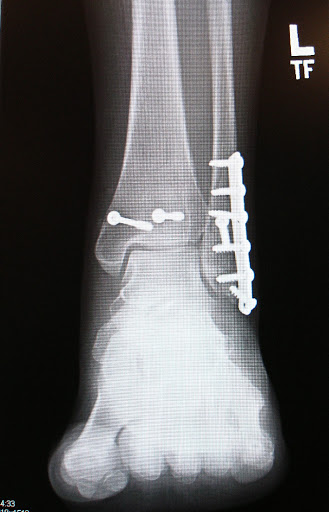

And this is an X-Ray of what my ankle looks like after surgery. The best part: you can actually feel one of the screw-heads right through my skin: